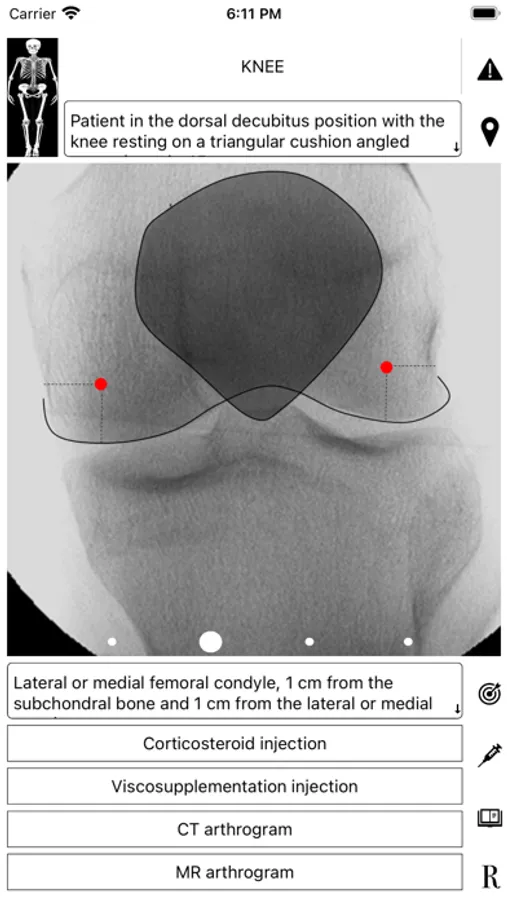

ArthroGuide targets residents, fellows, and physicians who perform fluoroscopically guided arthrograms and pain management injections, including spinal injections. It results from more than 25 years of experience in performing and teaching these procedures.

A visual interface facilitates a quick and efficient review of the information. Find information on patient positioning, puncture site, equipment used, products injected, and the steps to perform therapeutic injections and arthrograms preliminary to an MRI or CT scan. Access relevant references online using hyperlinks directly from within the application. Take advantage of procedural tips, recommendations, and cautionary statements.

ArthroGuide Screenshots